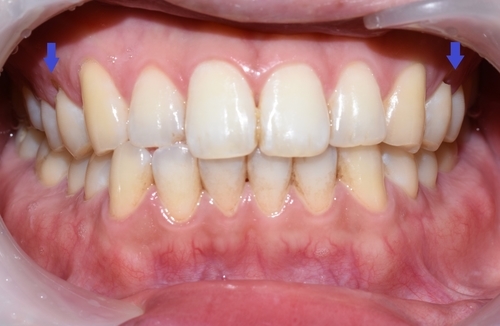

치료 전 모습으로 치아가 누렇고 착색이 있으며, 치아 패인 부분이 있음(화살표)

구강검진 후 스케일링,치아 패인곳(화살표) 떼우기, 원데이2회미백을 진행하기로 상담하였으며

몇 달 동안 커피를 매일 드셨지만 그래도 처음에 비하면 잘 유지된 모습입니다.

이번에도 치아미백2회 진행하였습니다.

예전에 미백을 하신 상태이므로 이미 애초보다는 밝은 치아였지만 거기서 또 밝아진 것을 볼 수 있습니다.

(미백 진행 전 후 같은 날 사진입니다)

이번에는 미백을 한번도 하지 않았던 상태와 미백2회 진행을 2번 하신 후를 비교해 볼까요?

미백 외에도 스케일링, 화살표 부분 떼우는 치료를 하셨습니다.

치아가 매우 환하고 깨끗해진 것을 한눈에 볼 수 있습니다.